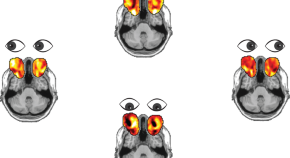

• Using a deep neural network, Frey et al. are able to track participants’ eye movements using functional magnetic resonance imaging of the eyes. This technique can be applied across studies to new and old data alike, allowing retrospective analyses of past studies.

• Ian Krajbich

News & Views

Nature Neuroscience

Volume: 24, P: 1641-1642